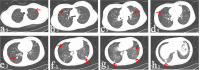

Materials and methods: We retrospectively reviewed seven patients with pulmonary metastatic GCT who received denosumab treatment after local tumor surgery during January 2014 and July 2016. Denosumab treatment for all patients lasted for at least 12 months. Serial chest computerized tomography scan was used to monitor the drug response and RECIST 1.1 standard was used to evaluate the therapeutic efficacy.

Results: All patients experienced chest pain relief in the first month of treatment. Three patients showed partial response. Four patients got stable disease after denosumab treatment. Adverse events included one patient with hypocalcemia and two patients with fever. No treatment-related deaths were reported. No patient with metastatic disease progression was found during an average of 28.6 months follow-up period.